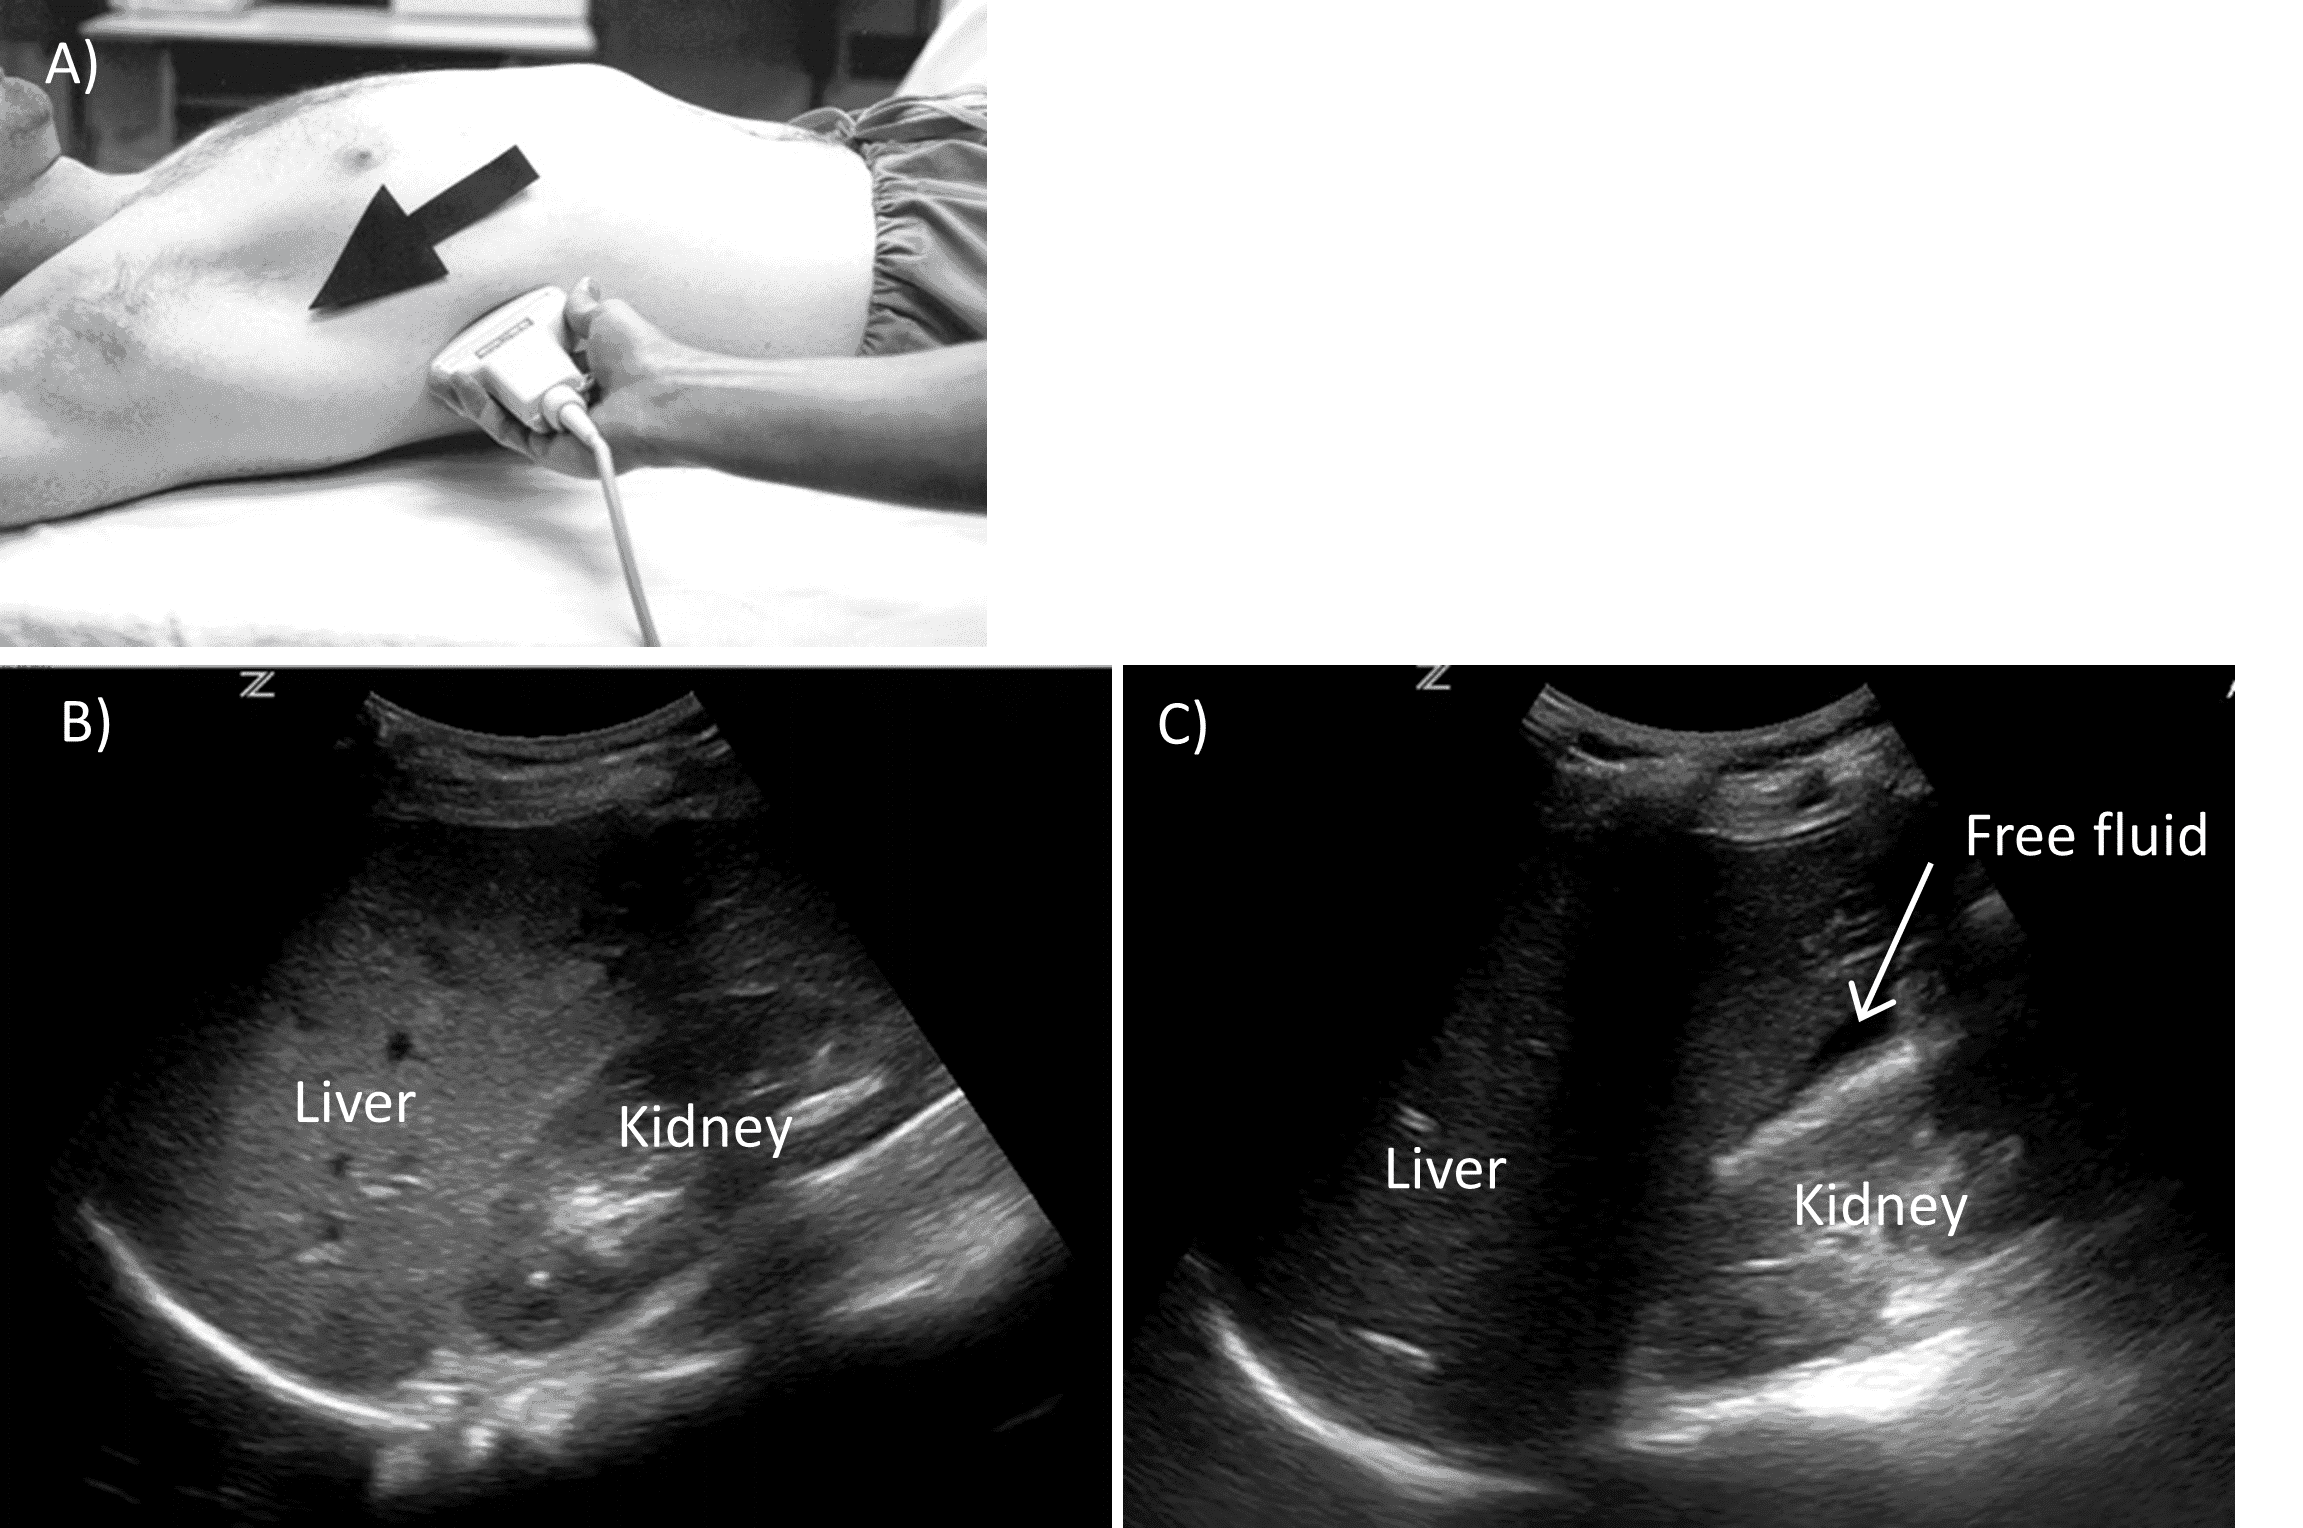

The right flank view is obtained by placing the probe between the midclavicular and posterior axillary lines near the 10th or 11th intercostal space with the probe indicator facing the patient’s head (Figure 5).

Right Flank View.

A) Probe positioning. B) Normal view. C) Positive view with free fluid.

The goal is to visualize the liver tip, the hepatorenal recess (Morison’s Pouch) and the hepatodiaphragmatic space. As no two individuals have the same anatomy, the exact position on initial placement is less important than a willingness to adjust based on what is visualized. Our approach is to attempt identification of the kidney with our probe placement. If we cannot capture the kidney in our view but visualize the liver, we know to move inferiorly, or vice versa. The probe is then fanned anteriorly and posteriorly to systematically evaluate Morison’s pouch and the interface between the kidney and the liver.

Sometimes this view can be challenging to obtain due to rib shadowing. Rib shadowing may be minimized by moving the probe up or down rib spaces or by rotating the probe counterclockwise to position it more parallel to the ribs. Paradoxically, often centering the probe directly onto the rib and then slightly adjusting position to “look over” the rib can be an effective technique to provide a clear view devoid of rib shadow.